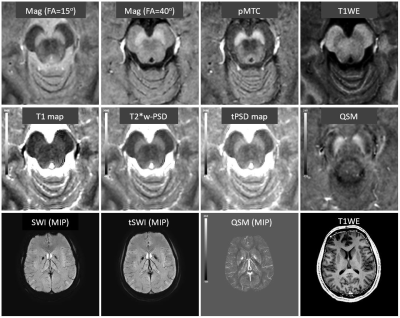

Figure 1. Representative images from MTC-STAGE for a 30 year old healthy male. Two scans were acquired with MTC: FA=15° and FA=40°. The product of these to MTC images (pMTC) gives a compromise exhibiting good contrast in both the upper and lower regions. Meanwhile, the STAGE processing gave SWI, tSWI, QSM and a T1WE image (neither of the two FA MTC datasets gave T1W images) as well as four quantitative data sets: a T1 map, T2* weighted PSD map, true-PSD (or tPSD) map, and QSM. The T1 map and PSD maps demonstrated that the MT contrast mainly occurs because of the high proton spin density in the NM.